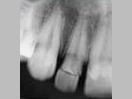

X-ray

Pre-Operation

Treating Non-Vital Tooth with Apical Pathology with the help of MTA

After 3 months

x-ray post operation

After 2 years